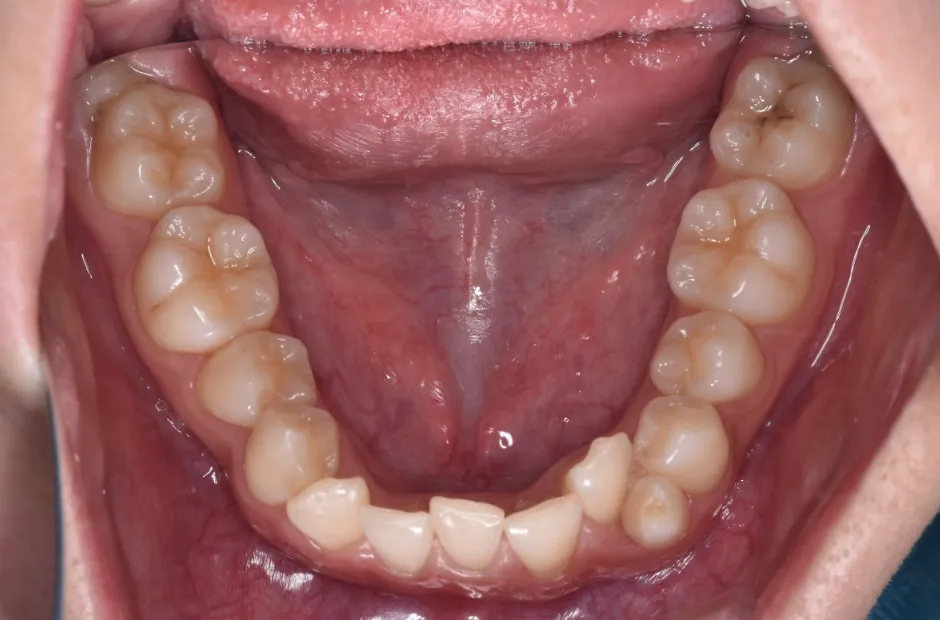

叢生

| 診断名・主訴 | 叢生 |

|---|---|

| 年齢・性別 | 43歳・女性 |

| 治療期間・回数 | 2年7か月 27回 |

| 治療に用いた主な装置 | 舌側矯正 |

| 抜歯部位 | 両顎4,4 |

| 治療費 | 100万円(税抜) |

| リスク・副作用 | 装置による違和感・疼痛・歯肉退縮・歯根吸収・虫歯のリスクなど |

治療前

治療中

治療後